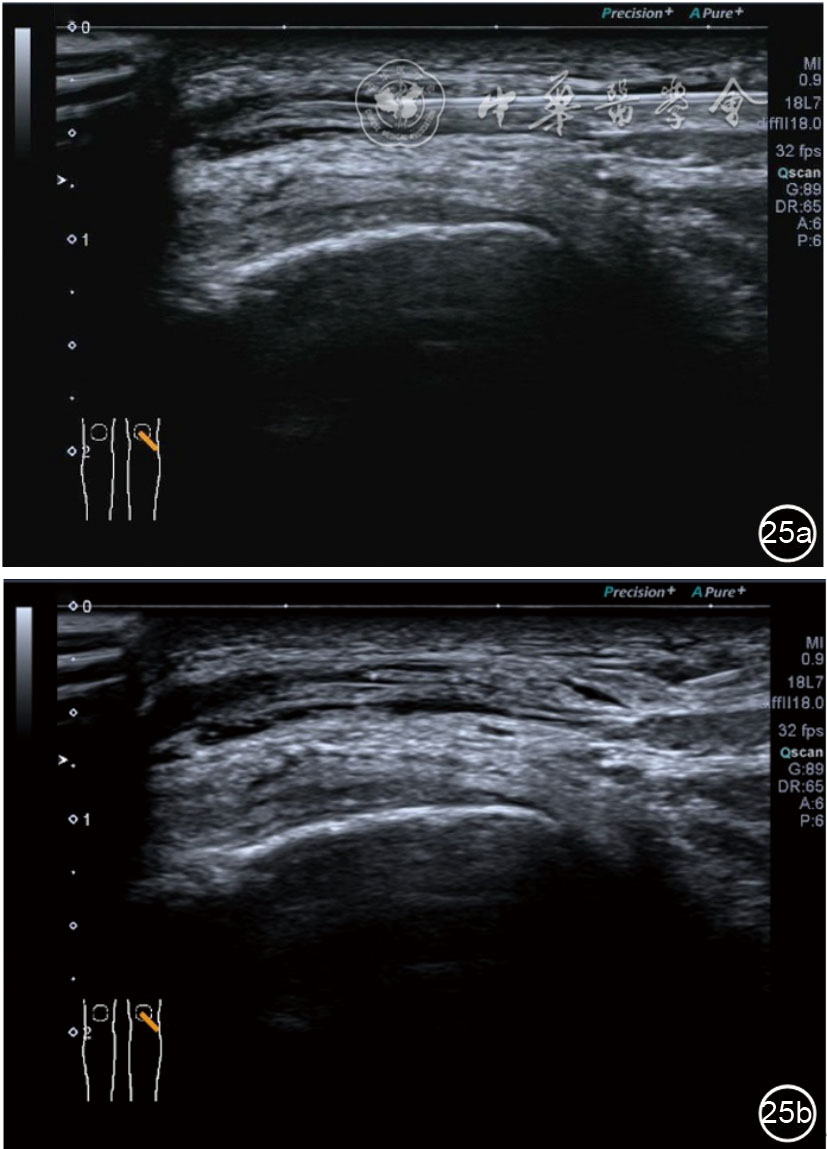

4.神经卡压液压松解加药物注射治疗。膝关节神经卡压主要涉及膝内上支、膝外上支、膝内下支、髌下支。可根据神经支配区域的临床检查确定卡压神经。临床上隐神经髌下支卡压常见。隐神经髌下支从隐神经发出后穿缝匠肌至膝内前下方,与深筋膜紧密相连(图24)。隐神经髌下支卡压出现膝关节内下侧酸痛、麻木,胫骨内侧髁压痛阳性,Tinel征阳性,局部皮肤痛觉减退。确定诊断后可行隐神经髌下支液压松解。患者平卧位,膝关节屈曲30°,下面垫一软枕。一般选用10 MHz以上超声探头,穿刺区域常规消毒,探头涂抹耦合剂后套入无菌手套碘伏消毒或使用无菌耦合剂。首先扫查神经短轴切面,确定神经后旋转为长轴切面引导注射。选用25G穿刺针头,抽吸0.5%利多卡因4 ml+地塞米松3 mg,从近端穿刺,沿神经表面纵轴方向,确定针尖在神经膜外后推注药物进行松解,注射完毕后拔出针头(图25),局部压迫2分钟,创可贴覆盖。

图24 隐神经髌下支卡压超声图像

图25 超声引导下隐神经髌下支卡压液压松解加药物注射治疗